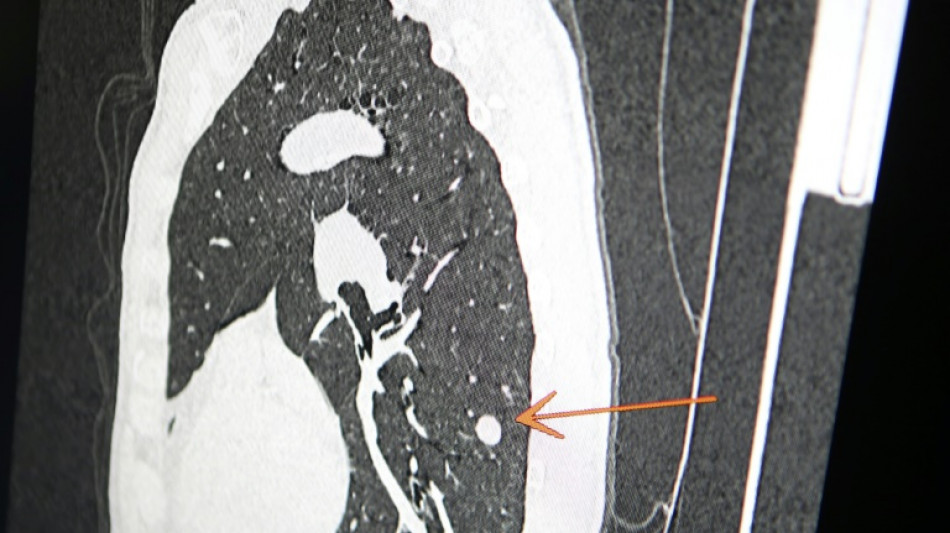

"Usted tiene cáncer", mensaje erróneo y aterrador a cientos de pacientes de una clínica en Inglaterra / Foto: © AFP/Archivos